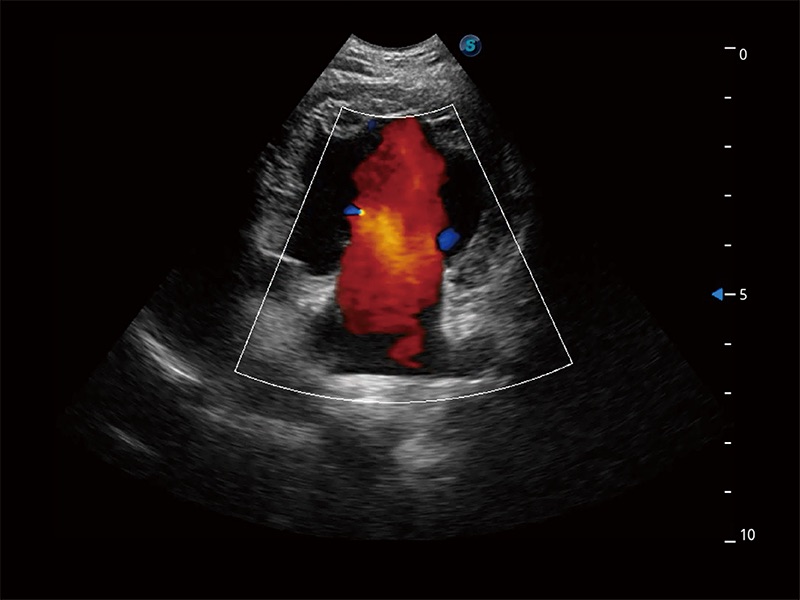

極大提升超低速微細(xì)血流的檢出能力,同時(shí)更精準(zhǔn)地濾除軟組織和超聲信號(hào),為獸用醫(yī)生提供以往無(wú)法通過(guò)常規(guī)血流獲得的疾病診斷信息。

在傳統(tǒng)二維血流成像的基礎(chǔ)上,呈現(xiàn)血流的立體感,具有動(dòng)感的生命力之美。即便是微小的血管也能輕松應(yīng)對(duì),提高了血流的視覺敏感性。